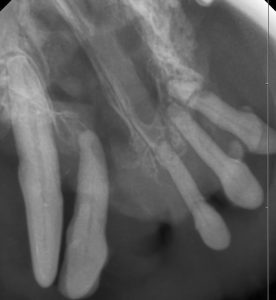

下の写真を見てみましょう。

左上顎の第四前臼歯が破折しています。

この子は左頬が腫れてしまい飼い主さんがすぐに気づき、セカンドオピニオンで受診されました。

この子の歯は露髄も伴う上、頬が腫れている症状は歯根膿瘍が起こっていると予測されます。

破折後の時間経過も長く、歯科レントゲンでは根尖病変を認めたため、抜歯をお勧めしました。